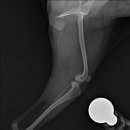

• 24시 에피소드 동물 메디컬 센터 | 만촌동 동물병원 강아지 요골·척골 골절 수술 후기 [24시에피소드동물메디컬센터]

만촌동 동물병원 강아지 요골·척골 골절 수술 후기 [24시에피소드동물메디컬센터] 만촌동 동물병원 ​ 안녕하세요. ​ 풍부한 경험과 따듯한 진료를 바탕으로, 반려동물의 건강하고 행복한 하루하루를 함께 만들어 가는 만촌동 동물병원 24시에피소드동물메디컬센터 입니다. 24시에피소드동물메디컬센터 대구광역시 동구...

에피소드동물메디컬센터(2025-06-26 12:41:00)